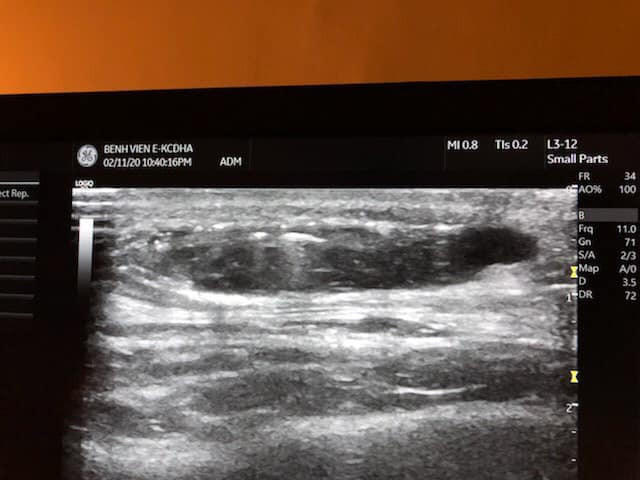

Ngay sau khi bệnh nhân nhập viện, ThS. BS. Nguyễn Đình Minh đã chỉ định siêu âm phát hiện thái dương bên trái có khối tụ dịch cách bề mặt da 3mm, kích thước 35 x 8 mm; vùng bên phải đã đặt chất liệu, không tụ dịch.